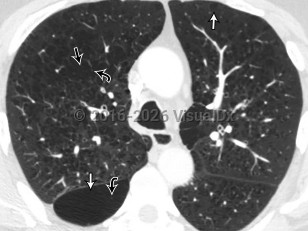

Pulmonary emphysemaPulmonary emphysema

Acute eosinophilic pneumoniaAcute eosinophilic pneumonia